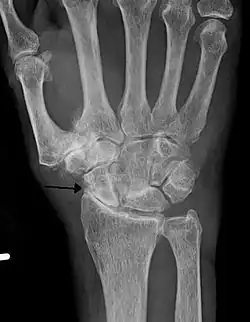

Severe osteoarthritis and osteopenia of the carpal joint and 1st carpometacarpal joint -

Primary osteoarthritis of the left knee. Note the osteophytes, narrowing of the joint space (arrow), and increased subchondral bone density (arrow). -